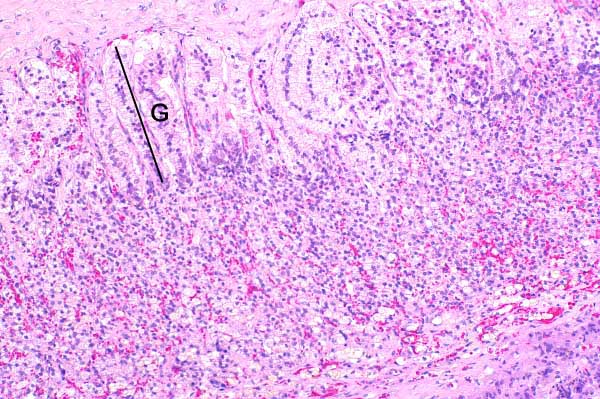

10x   |   Hematoxylin and Eosin

The zona fasciculata and zona reticularis are severely atrophied.